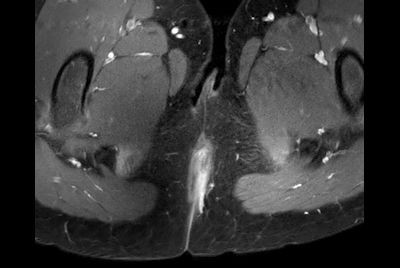

mDIXON XD TSE - Ankle tumor